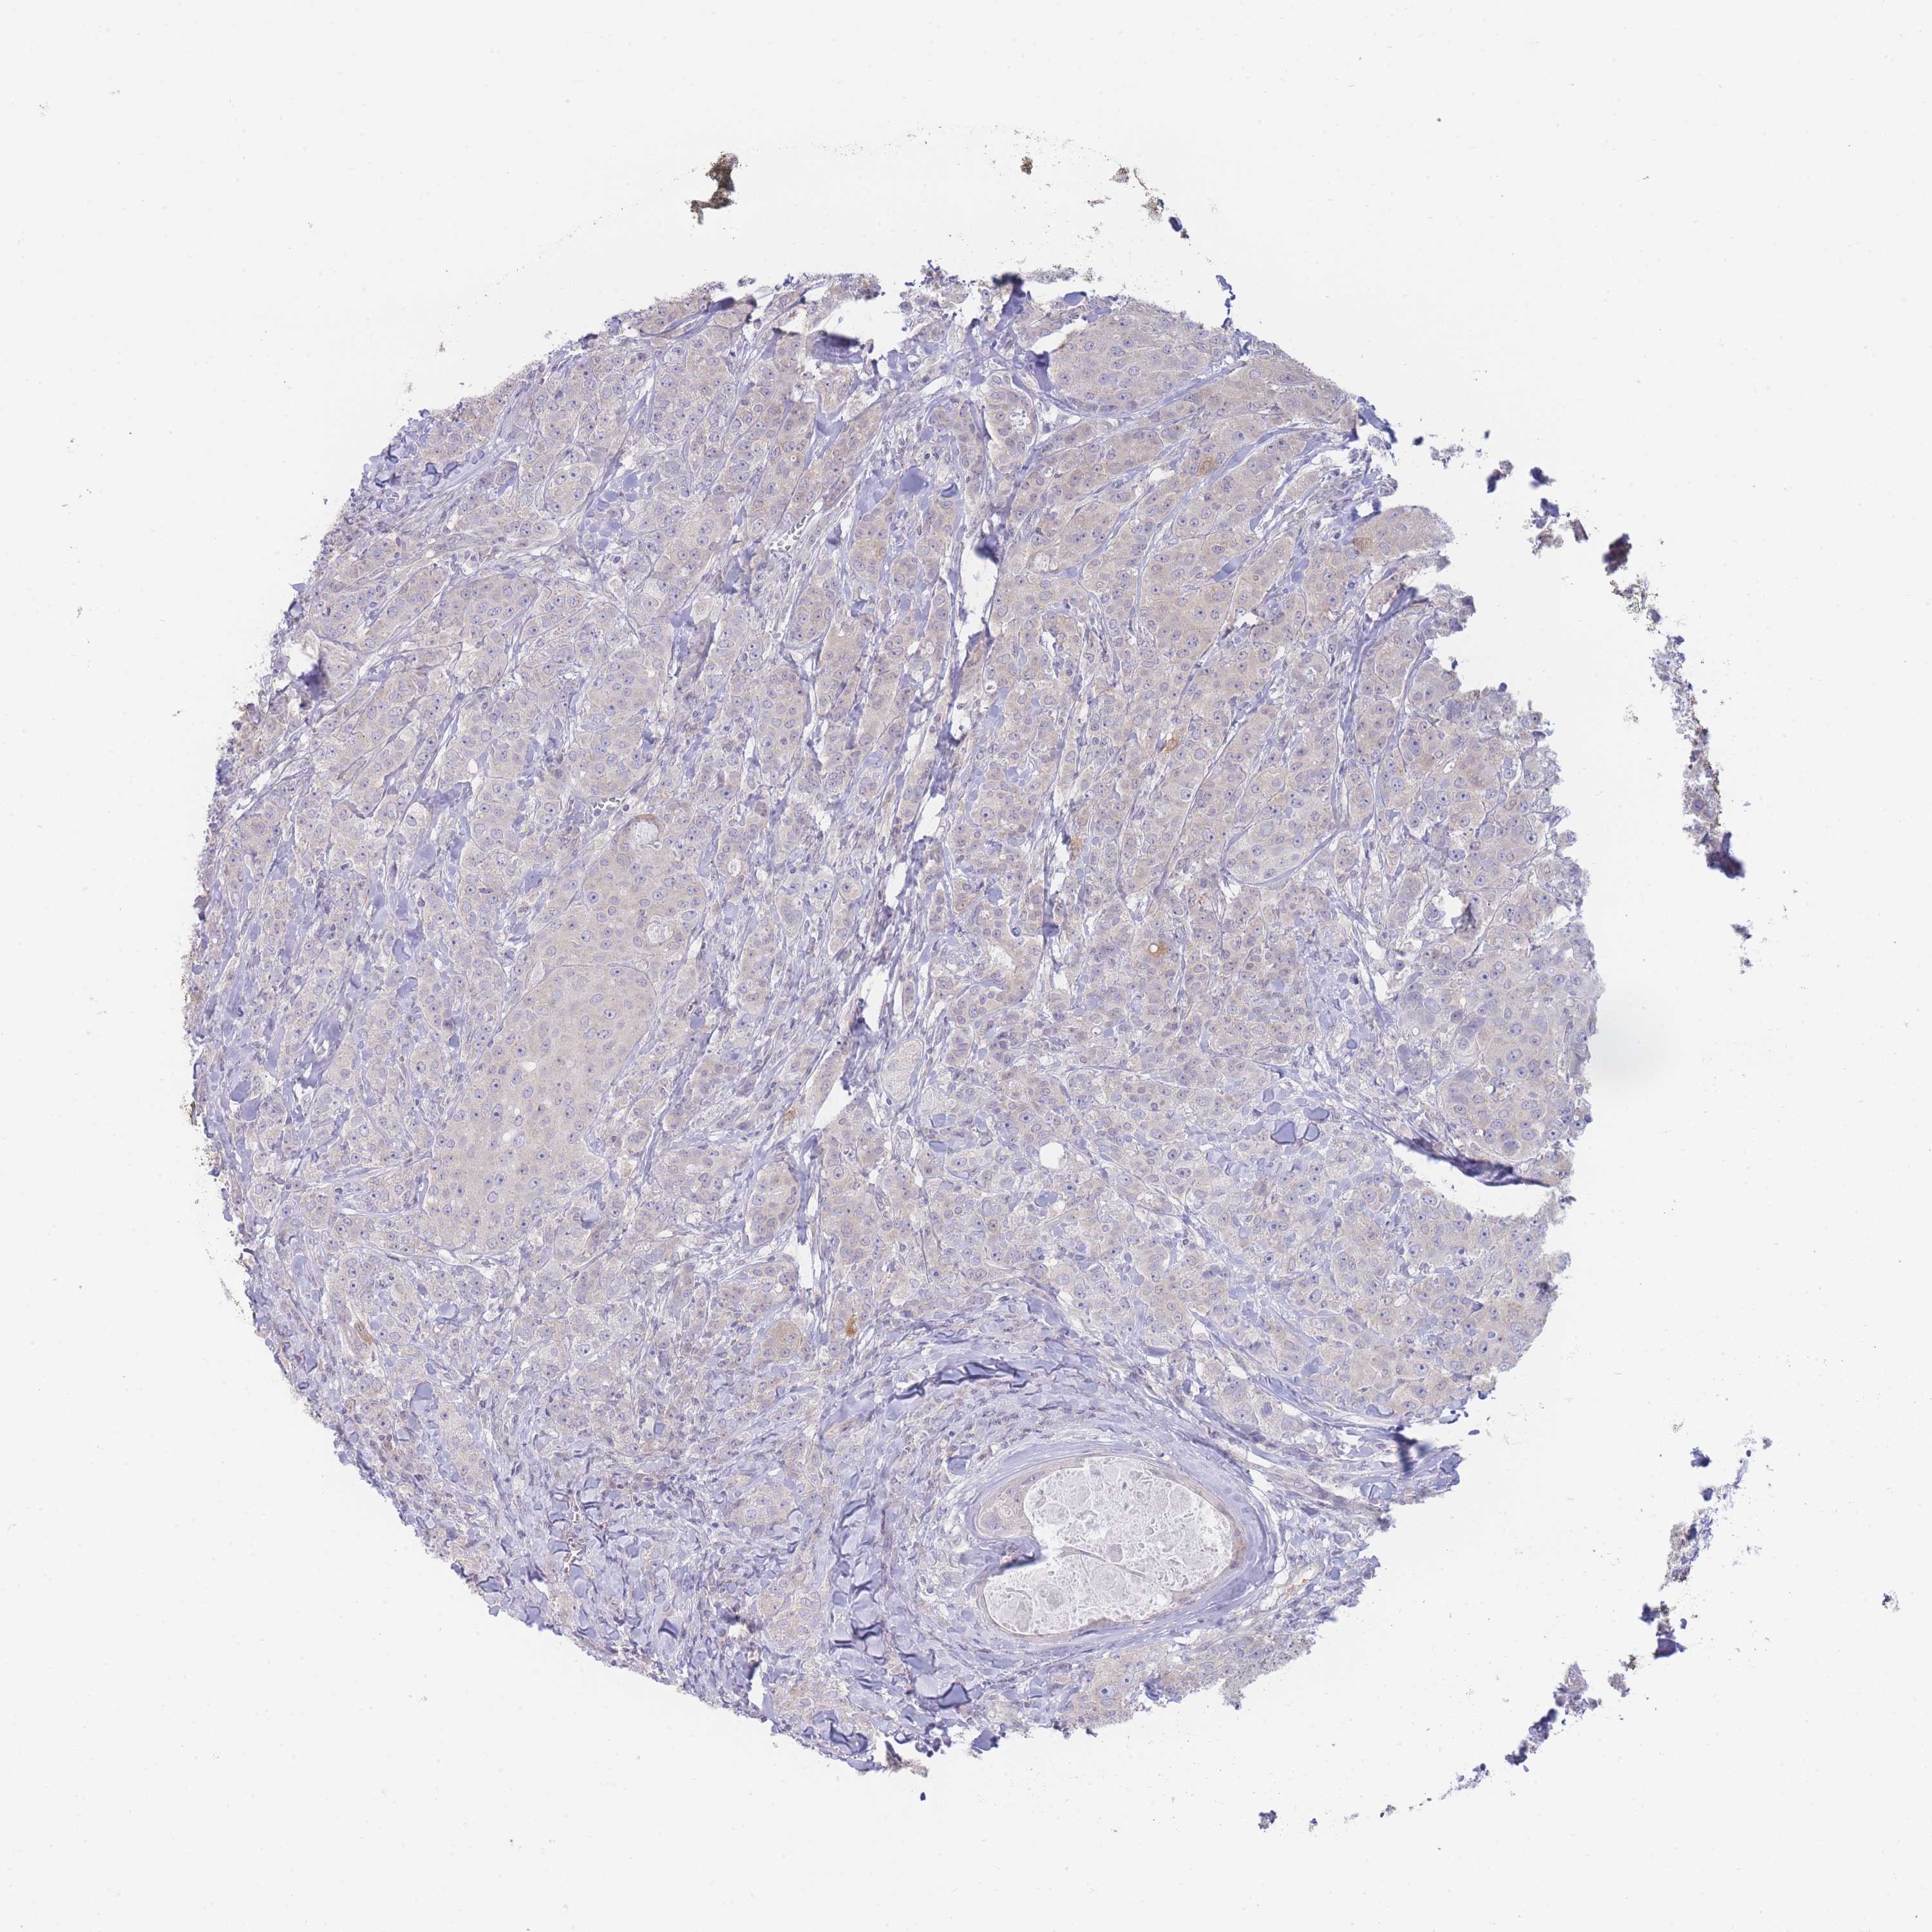

BRCA TCGA BRCA VALIDATION PROTEIN EXPRESSION

ANTIBODIES

AND

VALIDATION